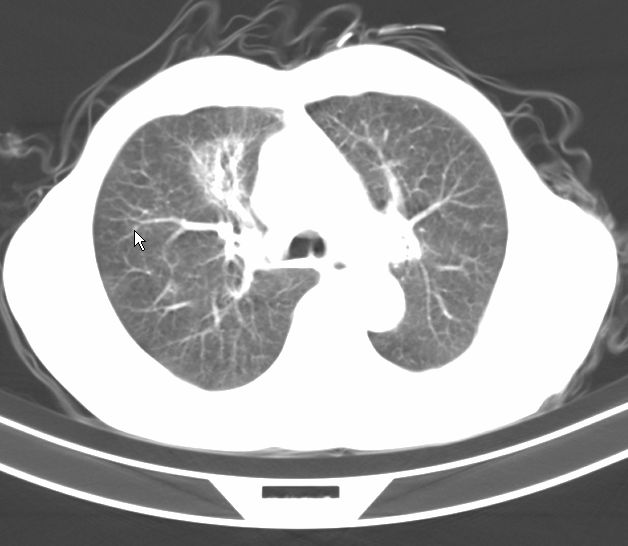

标题: CT17095:胸部病变请大家看看是什么性质的

请大家看看是什么性质的。炎性病变首先考虑哪一种炎症。

支持右肺上叶前段\\下叶内基底段感染,建议抗炎治疗后复查,除外结核.

支持右肺上叶前段\\下叶上段感染,建议抗炎治疗后复查,除外结核.

支持右肺上叶前段、下叶内基底段感染,建议抗炎治疗后复查,除外结核.

右肺上叶前段及下叶内基底段感染性病变;建议抗炎治疗后复查。

楼主说是炎症,凭啥?典型的周围型肺癌(腺癌可能性大),肝内可能已有转移,强化看看吧。